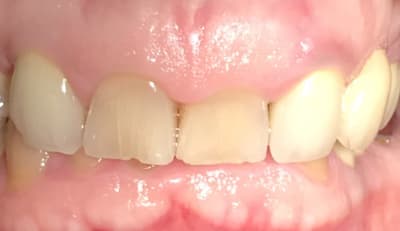

En attendant que le nouveau réponde ... Dans un style différent : 38 ans . très complexé. Aucun dentiste n’a voulu le toucher (pour le secteur antérieur) . Je lui ai dit qu’il fallait lui déglinguer la mâchoire. Sauf qu’il ne veut pas faire de chirurgie orthognatique, c’est sa seule condition . Par contre est prêt à mettre n’importe quel prix pour retrouver un beau sourire. N’est ni fermé à l’ortho , ni fermé à l’implantologie.

Photo de la pano qu’il m’a ramenée.

On se passera des : faut faire un détartrage :) , ou faut qu’il se lave les dents.

Ex des centrales et bridge 12-22, je pense que tu peux faire un truc sympa. Teste sur ton plâtre.

Ça c’est un cas qui s’apparente au cas du nouveau . Le problème dans ce genre de cas traité uniquement prophétiquement c’est qu’on n’obtient pas forcément une meilleure occlusion :) .

Dans le cas du nouveau il faut vraiment faire une intervention osseuse ++++, encore plus que sur celle-ci

Sur celle là il y a eu quoi ? Elongation ou bien impaction du bloc ant ?

Celle-ci c’était élongation et plusieurs implants en postérieur.

À la base elle était juste venue pour ne plus avoir de sourire gingivale. J’ai commencé par le secteur antérieur. Sauf que quelque part ses dents antérieures lui stabilisaient son occlusion. Aussitôt que je lui ai fait le secteur antérieur, qu’elle s’est plainte de ses articulations . Donc j’ai tout de suite posé des implants en postérieur et mis des couronnes , et aussitôt plus de problème. Il aurait fallu commencer par ça. Mais bon comme ils ne jurent que par l’esthétique, c’est toujours le problème. Et c’est une fois qu’ils sont en confiance que certains se décident à faire le postérieur.